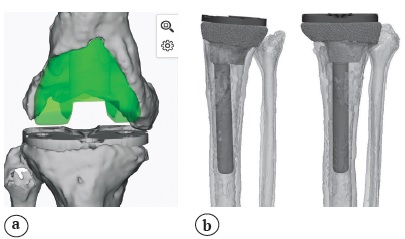

Preoperative planning and implant production

Multislice spiral computed tomography (CT) with 1 mm-thick slices and full-length X-rays of lower extremities (Full Leg Full Spine — FLFS) were taken at the first stage in order to produce custom-made implants. Then a three-dimensional computer model of the knee joint was created. It was followed by the simulation of the bone defect surface with the use of cut and crop tools that allowed to remove artifacts and hypertrophic scars visualized as bone structures. Afterwards the 3D model of the proximal part of the tibia and/or distal part of the femur of the intact (contralateral) joint was mirrored with its following precision positioning to the place of the bone defect in order to replace the latter. Then the Boolean substruction operation was carried out to produce 3D model of the custom-made implant. Pores were made on the implant surface for better osteointegration. The following topologic 3D implant refinement was performed using the SIMP method (Fig. 1). Finally, the implant was 3D printed using Titanium-Aluminium-Vanadium (Ti6Al4V) alloy and sterilized.

Fig. 1. The stage of computer modeling of an individual implant for the replacement of the distal femur (а) and proximal tibia (b) bone defect